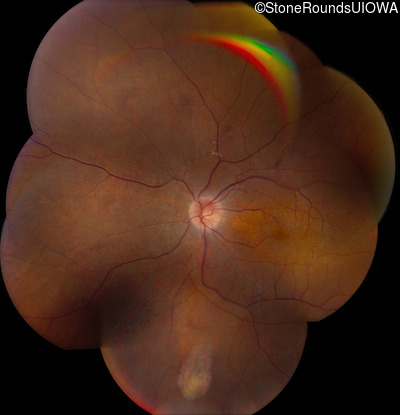

Bardet Biedl Syndrome (IB2)

Visit at age: 11 years

Fundus Montage - Right - 20/50 +1

Exemplar

Fundus Montage - Left - 20/50 +1